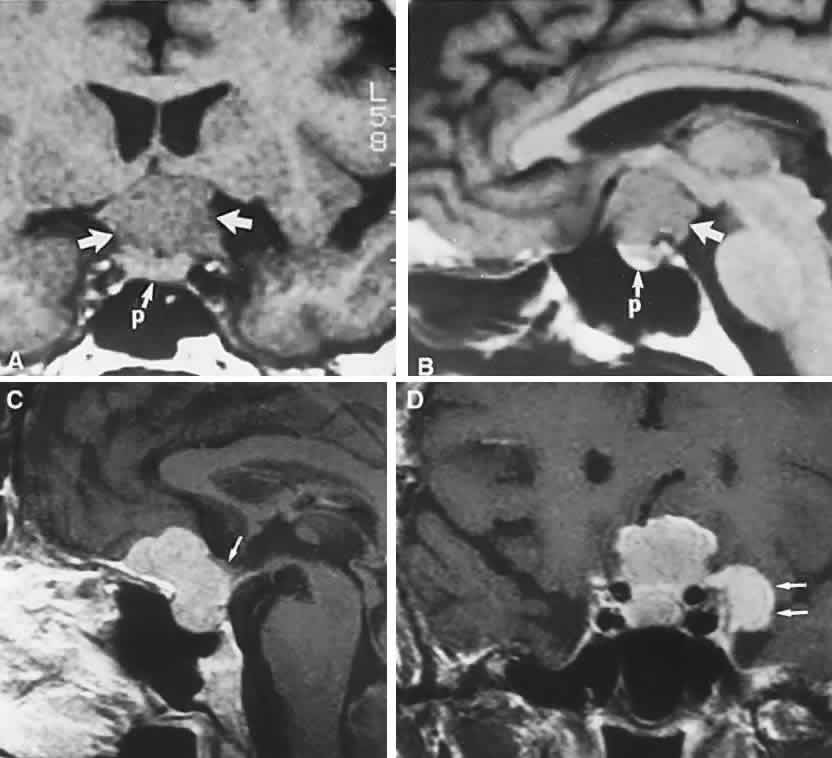

adults. Acta Paediatr 84:1382, 1995 167. McGrath P: Cysts of sellar and pharyngeal hypophyses. Pathology 3:123, 1971 168. Benes SL, Kansu T, Savino PJ et al: Ocular manifestations of arachnoid

cysts. In Glaser JS (ed): Neuro-Ophthalmology: Symposium of the University

of 38 cases. J Neurosurg 60:8, 1984 172. Appen RE, deVenecia G, Selliken JM, Giles LT: Meningeal carcinomatosis with blindness. Am J Ophthalmol 86:661, 1978 173. Takahashi T, Murase T, Isayama Y: Clinicopathological findings in the chiasmal

region with reference to carcinomatous optic neuropathy cases. In

Shimizu K, Oosterhuis JA (eds): Ophthalmology, Vol 2, p 1124. Amsterdam, Excerpta

Medica, 1979 174. Takahashi T, Yoshimasa I: Pathological findings in the chiasmal region with reference to malignant

lymphoma. Folia Ophthalmol Jpn 31:1118, 1980 175. Howard RS, Duncombe AS, Owens C et al: Compression of the optic chiasm due to a lymphoreticular malignancy. Postgrad Med J 63:1091, 1987 176. Tabarin A, Corcuff JB, Dautheribes M et al: Histiocytosis X of the hypothalamus. J Endocrinol Invest 14:139, 1991 177. Max MB, Deck F, Rottenberg DA: Pituitary metastases: incidence in cancer patients and clinical differentiation

from pituitary adenoma. Neurology 31:998, 1981 178. Woiciechowsky C, Vogel S, Meyer R et al: Magnetic resonance imaging of a glioblastoma of the optic chiasm: case

report. J Neurosurg 83:923, 1995 179. Liu GT, Galetta SL, Rorke LB et al: Gangliogliomas involving the optic chiasm. Neurology 46:1669, 1996 180. Morrison DA, Bibby K: Sellar and suprasellar hemangiopericytoma mimicking pituitary adenoma. Arch Ophthalmol 115: 1201, 1997 181. Balcer LJ, Galetta SL, Curtis M: von Hippel-Lindau disease manifesting as a chiasmal syndrome. Surv Ophthalmol 39: 302, 1995 182. Teixeira F, Penagos P, Lozano D et al: Medulloblastoma pre-senting as blindness of rapid evolution: a case report. J Clin Neuroophthalmol 11:250, 1991 183. Goodwin JA, Glaser JS: Chiasmal syndrome in sphenoid sinus mucocele. Ann Neurol 4:440, 1978 184. Valvassori GE, Putterman AM: Ophthalmologic and roentgenographic findings in sphenoidal mucoceles. Trans Am Acad Ophthalmol Otolaryngol 77:703, 1973 185. Abla AA, Maroon JC, Wilberger JE et al: Intrasellar mucocele simulating pituitary adenoma: case report. Neurosurgery 18: 197, 1986 186. Heinz GW, Nunery WR, Grossman CB: Traumatic chiasmal syndrome associated with midline basilar skull fractures. Am J Ophthalmol 117:90, 1994 187. Elisevich KV, Ford RM, Anderson DP et al: Visual abnormalities with multiple trauma. Surg Neurol 22:565, 1984 188. Savino PJ, Glaser JS, Schatz NJ: Traumatic chiasmal syndrome. Neurology 30:963, 1980 189. Ess T, Weiler G: Histomorphologische Befunde and Chiasma opticum bei Schadel-Hirntrauma. Z Rechtsmed 82:257, 1979 190. Crompton MR: Hypothalamic lesions following closed head injury. Brain 94:165, 1971 191. Arkin MS, Rubin AD, Bilyk JR et al: Anterior chiasmal optic nerve avulsion. AJNR Am J Neuroradiol 17:1777, 1996 192. Hayman A, Carter K, Schiffman JS et al: A sellar misadventure: imaging considerations. Surv Ophthalmol 41:252, 1996 193. Warman R, Glaser JS: Radionecrosis of optico-hypothalamic glioma. Neuroophthalmology 9:219, 1989 194. Kline LB, Kim JV, Ceballos R: Radiation optic neuropathy. Ophthalmology 92:1118, 1985 195. Ebner R, Slamovits TL, Friedland S et al: Visual loss following treatment of sphenoid sinus carcinoma. Surv Ophthalmol 40: 62, 1995 196. Atkinson AB, Allen IV, Gordon DS et al: Progressive visual failure in acromegaly following external pituitary irradiation. Clin Endocrinol 10:469, 1979 197. Hammer HM: Optic chiasmal radionecrosis. Trans Ophthalmol Soc UK 103:208, 1983 198. Girkin CA, Comey CH, Lunsford LD et al: Radiation optic neuropathy after stereotactic radiosurgery. Ophthalmology 104: 1634, 1997 199. Zimmerman CF, Schatz NJ, Glaser JS: Magnetic resonance imaging of radiation optic neuropathy. Am J Ophthalmol 110: 389, 1990 200. Hudgins PA, Newman NJ, Dillong WP et al: Radiation-induced optic neuropathy: characteristics on gadolinium-enhanced

MR. AJNR Am J Neuroradiol 13:235, 1992 201. Hufnagel TJ, Kim JH, Lesser R et al: Malignant glioma of the optic chiasm eight years after radiotherapy for

prolactinoma. Arch Ophthalmol 106:1701, 1988 202. Aristizabal S, Caldwell WL, Avila J: The relationship of time dose fractionation factors to complication in

the treatment of pituitary tumors by irradiation. Int J Radiat Oncol Biol Phys 2:667, 1977 203. Parsons JT, Bova FJ, Fitzgerald CR et al: Radiation optic neuropathy after megavoltage external-beam irradiation: analysis

of time-dose factors. Int J Radiation Oncol Biol Phys 30:755, 1994 204. Wilson WB, Perez GM, Kleinschmidt-Demasters BK: Sudden onset of blindness in patients treated with oral CCNU and low-dose

cranial irradiation. Cancer 59:901, 1987 205. Glantz MJ, Burger PC, Friedman AH et al: Treatment of radiation-induced nervous system injury with heparin and warfarin. Neurology 44:2020, 1994 206. Borruat FX, Schatz NJ, Glaser JS et al: Visual recovery from radiation-induced optic neuropathy: the role of hyperbaric

oxygen therapy. J Clin Neuroophthalmol 13:98, 1993 207. Borruat FX, Schatz NJ, Glaser JS: Radiation optic neuropathy: report of cases, role of hyperbaric oxygen

therapy, and literature review. Neuroophthalmology 16:255, 1996 208. Sinclair AHH, Dott NM: Hydrocephalus simulating tumour in the production of chiasmal and other

parahypophysial lesions. Trans Ophthalmol Soc U K 51:232, 1931 209. Hughes EBC: Some observations on the visual fields in hydrocephalus. J Neurol Neurosurg Psychiatry 9:30, 1946 210. Corbett JJ: Neuro-ophthalmologic complications of hydrocephalus and shunting procedures. Semin Neurol 6:111, 1986 211. Calogero JA, Alexander E: Unilateral amaurosis in a hydro-cephalic child with an obstructed shunt: case

report. J Neurosurg 34:236, 1971 212. Kupersmith MJ, Rosenberg C, Kleinberg D: Visual loss in pregnant women with pituitary adenomas. Ann Intern Med 121: 473, 1994 213. Roelvink NCA, Kamphorst W, van Alphen HAM et al: Pregnancy-related primary brain and spinal tumors. Arch Neurol 44:209, 1987 214. Abramsky O: Pregnancy and multiple sclerosis. Ann Neurol 36:38, 1994 215. Cosman F, Post KD, Holub DA et al: Lymphocytic hypophysitis: report of three new cases and review of the literature. Medicine 68:240, 1989 216. Sunness JS: The pregnant woman's eye. Surv Ophthalmol 32: 219, 1988 217. Kaufman B: The “empty” sella turcica, a manifestation of the intrasellar

subarachnoid space. Radiology 90:931, 1968 218. Bergland RM, Ray BS, Torack RM: Anatomical variations in the pituitary gland and adjacent structures in 225 human

autopsy cases. J Neurosurg 28:93, 1968 219. Zagardo MT, Cail WS, Kelman SE et al: Reversible empty sella in idiopathic intracranial hypertension: an indicator

of successful therapy. AJNR Am J Neuroradiol 17:1953, 1996 220. Neelon FA, Goree JA, Lebovitz HE: The primary empty sella: clinical and radiographic characteristics and

endocrine function. Medicine 52:73, 1973 221. Brismar K: Prolactin secretion in the empty sella syndrome in prolactinomas and in

acromegaly. Acta Med Scand 209:397, 1981 222. Tremoulet M, Petrus M, Bonafe A, Rochiccioli P: La selle turcique vide de l'enfant. Rev Otoneuroophthalmol 54: 405, 1982 223. Wilkinson IA, Duck SC, Gager WE, Daniels DL: Empty-sella syndrome: occurrence in childhood. Am J Dis Child 136:245, 1982 224. Berke JP, Buxton LF, Kokmen E: The “empty sella.” Neurology 25:1137, 1975 225. Olson DR, Guiot G, Derome P: The symptomatic empty sella: prevention and correction via the transsphenoidal

approach. J Neurosurg 37:553, 1972 226. Bursztyn EM, Lavyne MH, Aisen M: Empty sella syndrome with intrasellar herniation of the optic chiasm. AJNR Am J Neuroradiol 4:167, 1983 227. Kaufman B, Tomsak RL, Kaufman BA et al: Herniation of the suprasellar visual system and third ventricle into empty

sellae: morphologic and clinical consideration. AJNR Am J Neuroradiol 10:65, 1989 |